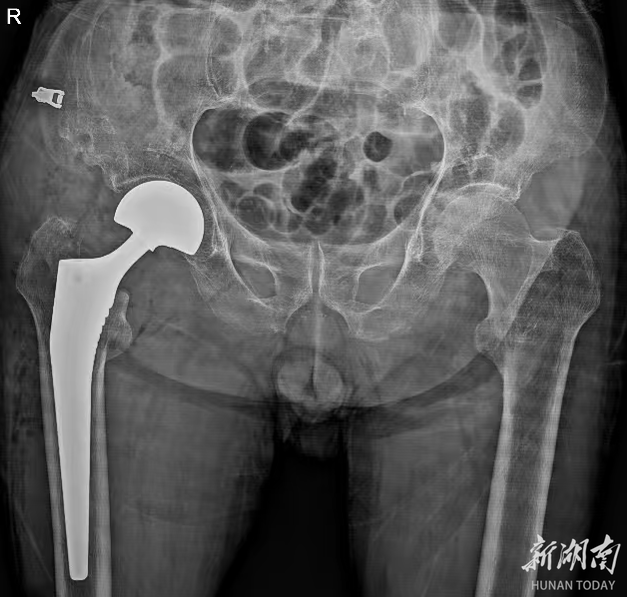

贺升建主任立即为易爷爷进行了详细的体格检查,并结合影像学检查结果,明确诊断为“陈旧性右侧股骨颈骨折”。贺主任介绍,陈旧性股骨颈骨折由于骨折端愈合不良,治疗难度远超新鲜骨折,再加上患者91岁高龄,合并多种基础疾病,手术风险极高,麻醉、术中出血、术后感染等都是需要攻克的难关。

为了给易爷爷制定全面专业的治疗方案,该院迅速启动多学科联合诊疗机制,召集了麻醉科、心血管内科、重症医学科等多个科室的专家进行联合会诊。专家们围绕易爷爷的骨折情况、基础疾病控制水平、手术耐受性等进行了全面深入的评估与讨论。心血管内科专家针对其高血压、冠心病病史,制定了术前血压、心率调控方案;麻醉科专家结合老人的身体状况,量身定制了创伤小、对循环影响小的麻醉方案;骨科团队则确定实施“右侧股骨颈骨折人工半髋关节置换术”。经过反复论证,专家们最终形成了一套周密的诊疗计划,为手术的顺利开展筑牢了安全防线。

在完成充分的术前准备后,手术如期进行。贺升建主任带领骨科手术团队凭借丰富的临床经验和精湛的操作技术,精准定位骨折部位,小心翼翼地进行关节置换操作。麻醉科团队全程严密监测易爷爷的生命体征,确保术中血流动力学稳定,整个手术过程一切顺利。